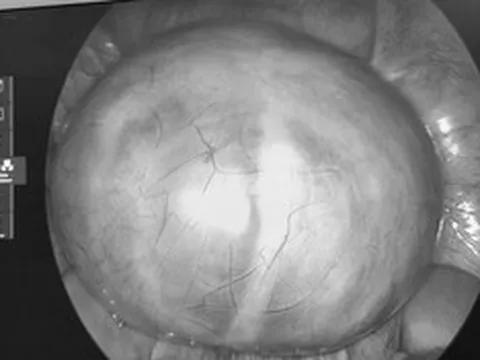

Người phụ nữ 42 tuổi đang khỏe mạnh bỗng ngất xỉu tử vong. Ảnh minh họa.